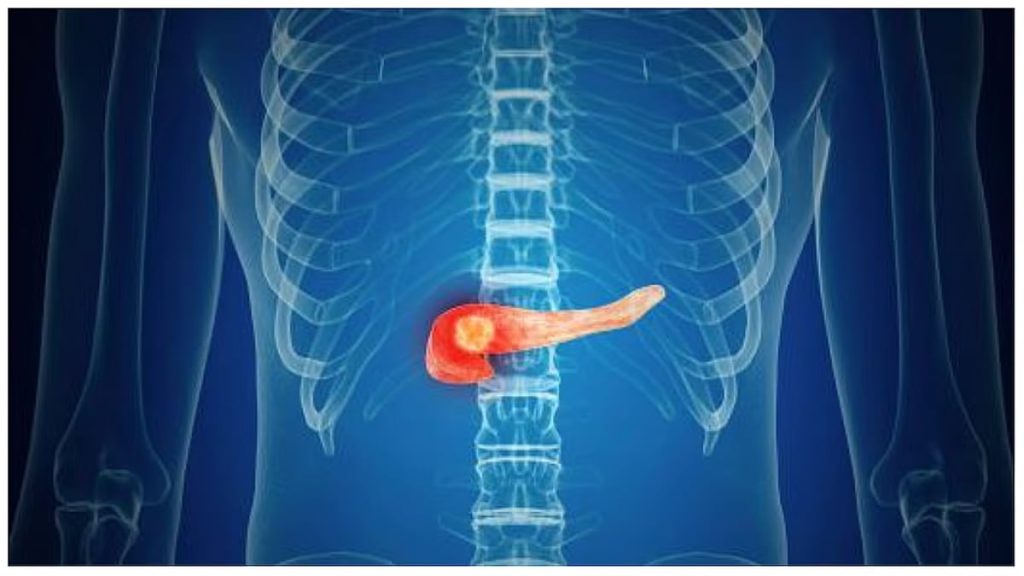

سرطان البنكرياس هو نمو غير طبيعي في خلايا البنكرياس، وغالباً يبدأ في الخلايا التي تبطن القنوات الحاملة للإنزيمات الهضمية، ويكتشف عادة متأخراً بسبب غياب الأعراض المبكرة.

ويعتمد علاج سرطان البنكرياس على صحة الإنسان ومكان ومرحلة الورم: